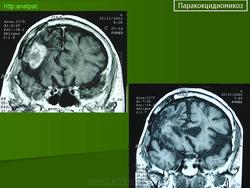

ГМ. Паракокцидиомикоз. +

Паракокцидиомикоз.

Множественные "узловые образования" имитирующие метастазы.